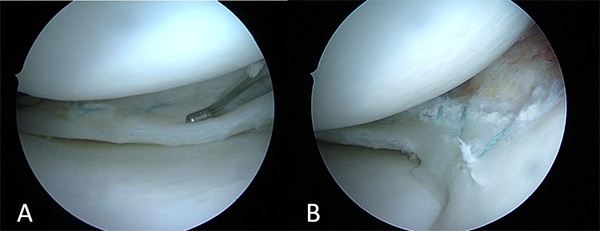

Se realizó la reducción del asa y luego se efectuó la sutura meniscal interna con tres Meniscal Cinch® (Arthrex, Naples, FL, EE. UU.) en tercio posterior y dos puntos fuera-dentro, verticales con FiberWire 2.0® (Arthrex, Naples, FL, EE. UU.) logrando una reducción y estabilidad satisfactorias (fig. 5).

Figura 5: Fijación de la lesión meniscal con cinco puntos, tres sistemas todo-adentro Meniscal Cinch® y dos puntos fuera-dentro.

Luego se efectuó un tercer portal transtendón rotuliano, y se realizó la reducción y fijación de la fractura de espina tibial con dos pines biodegradables SmartNail CONMED® de 1.5 mm de diámetro por 25 mm de longitud (fig. 6).

Figura 6: A) Fractura de espina tibial grado 3. B) Fijación con dos pines biodegradables.